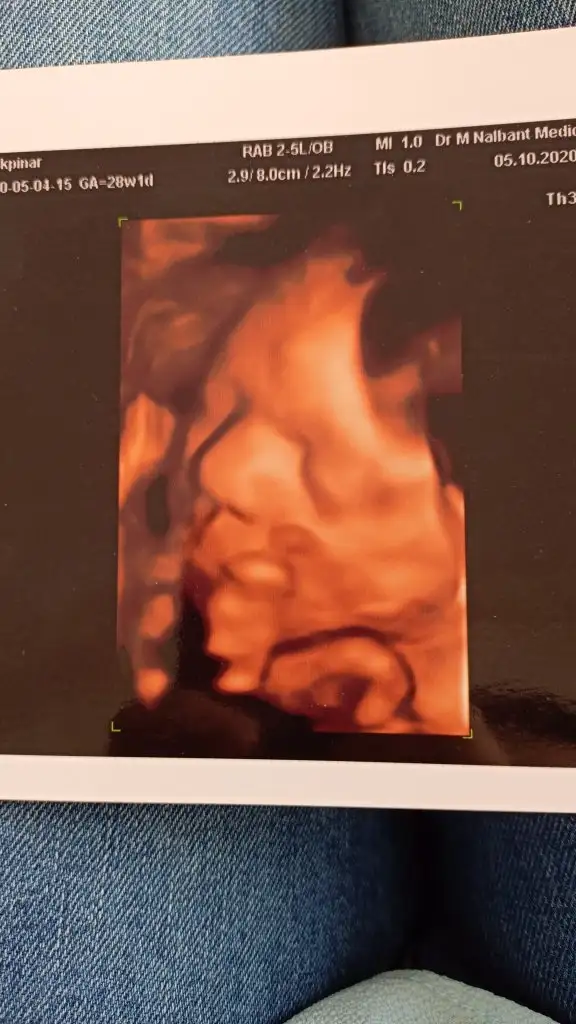

Kızlar kontrolden geldim çok şükür her şey yolunda kızım bayagi büyümüş 1400 kg 38 cm olmusuz masallah önde gidiyo gelişimi kan verdim sonuca göre uyusmazlik ignem yapılacak. Bide alnı sanki sis gibi doktora sorsam güler mi bana bilen biri yorum yapabilir mi su hacminden dolayimi mi böyle gorunuyo

• IMG-20201005-WA0000.webp

42,8 KB · Görüntüleme: 76

oy masallah yesin onu teyzesi

Maşallah yaaaa ne güzel poz yakalamışlar biz yüzüne hasretiniz kilosu da maşallahı war neler yiyorsun acaba sormusmuydum hatırlamıyorum sorduysam kusuruma bakma

Maşallah canım Allah nazarlardan saklasin alnı bence fotoğraftan kaynaklı öyle. Su içindeler ya. Bende ne fotolar var öyle degisik değişik. Korkma yani

Ay şimdi ilk bebişim ya takıldım kaldım kaç saattir yinede bı sorcam gülerse gülsün Allah korusun önlemi olmaz ama yinede içim rahatlasin banada öyle geliyo sudan dolayıdır burnuda kocaman cikiyo ama bebek doguyo minnak bisey